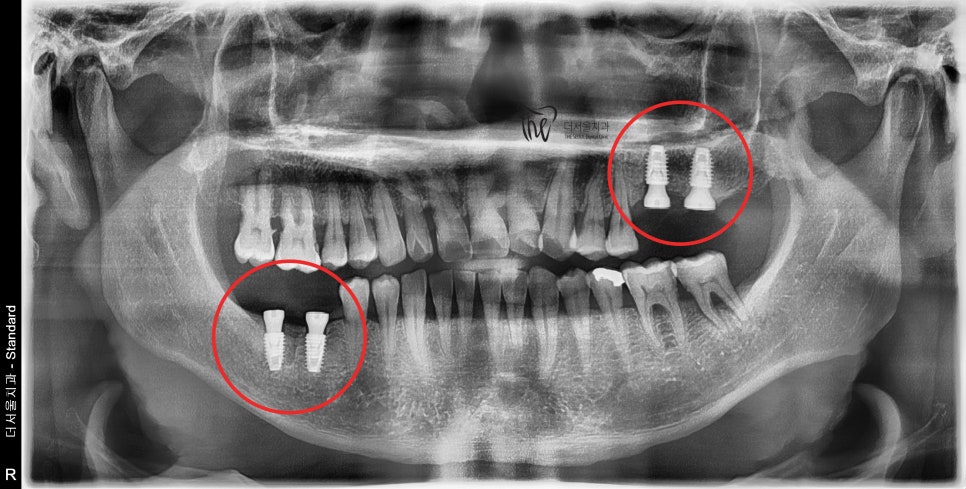

그 결과, 어금니 빠짐 이 있던 곳에

총 4개의 고정체들이 심겨졌으며 대략 2~3개월

가량 경과를 지켜본 뒤에 지르코니아 크라운을

올려드리기로 했었죠.

와.. 근데 이 분은 진짜로 금연을 실천하셨습니다.

꼭 금연 때문은 아니나, 생각보단 더 빠르게

뼈와 고정체가 달라붙었으며 예상보다 2주 가량

빠르게 어금니 빠짐 에 따른 문제들이 해결이

되었었습니다.

그래서, 더 빠르게 지르코니아 보철을

올려드리면서 치료를 끝내드릴 수 있었죠.